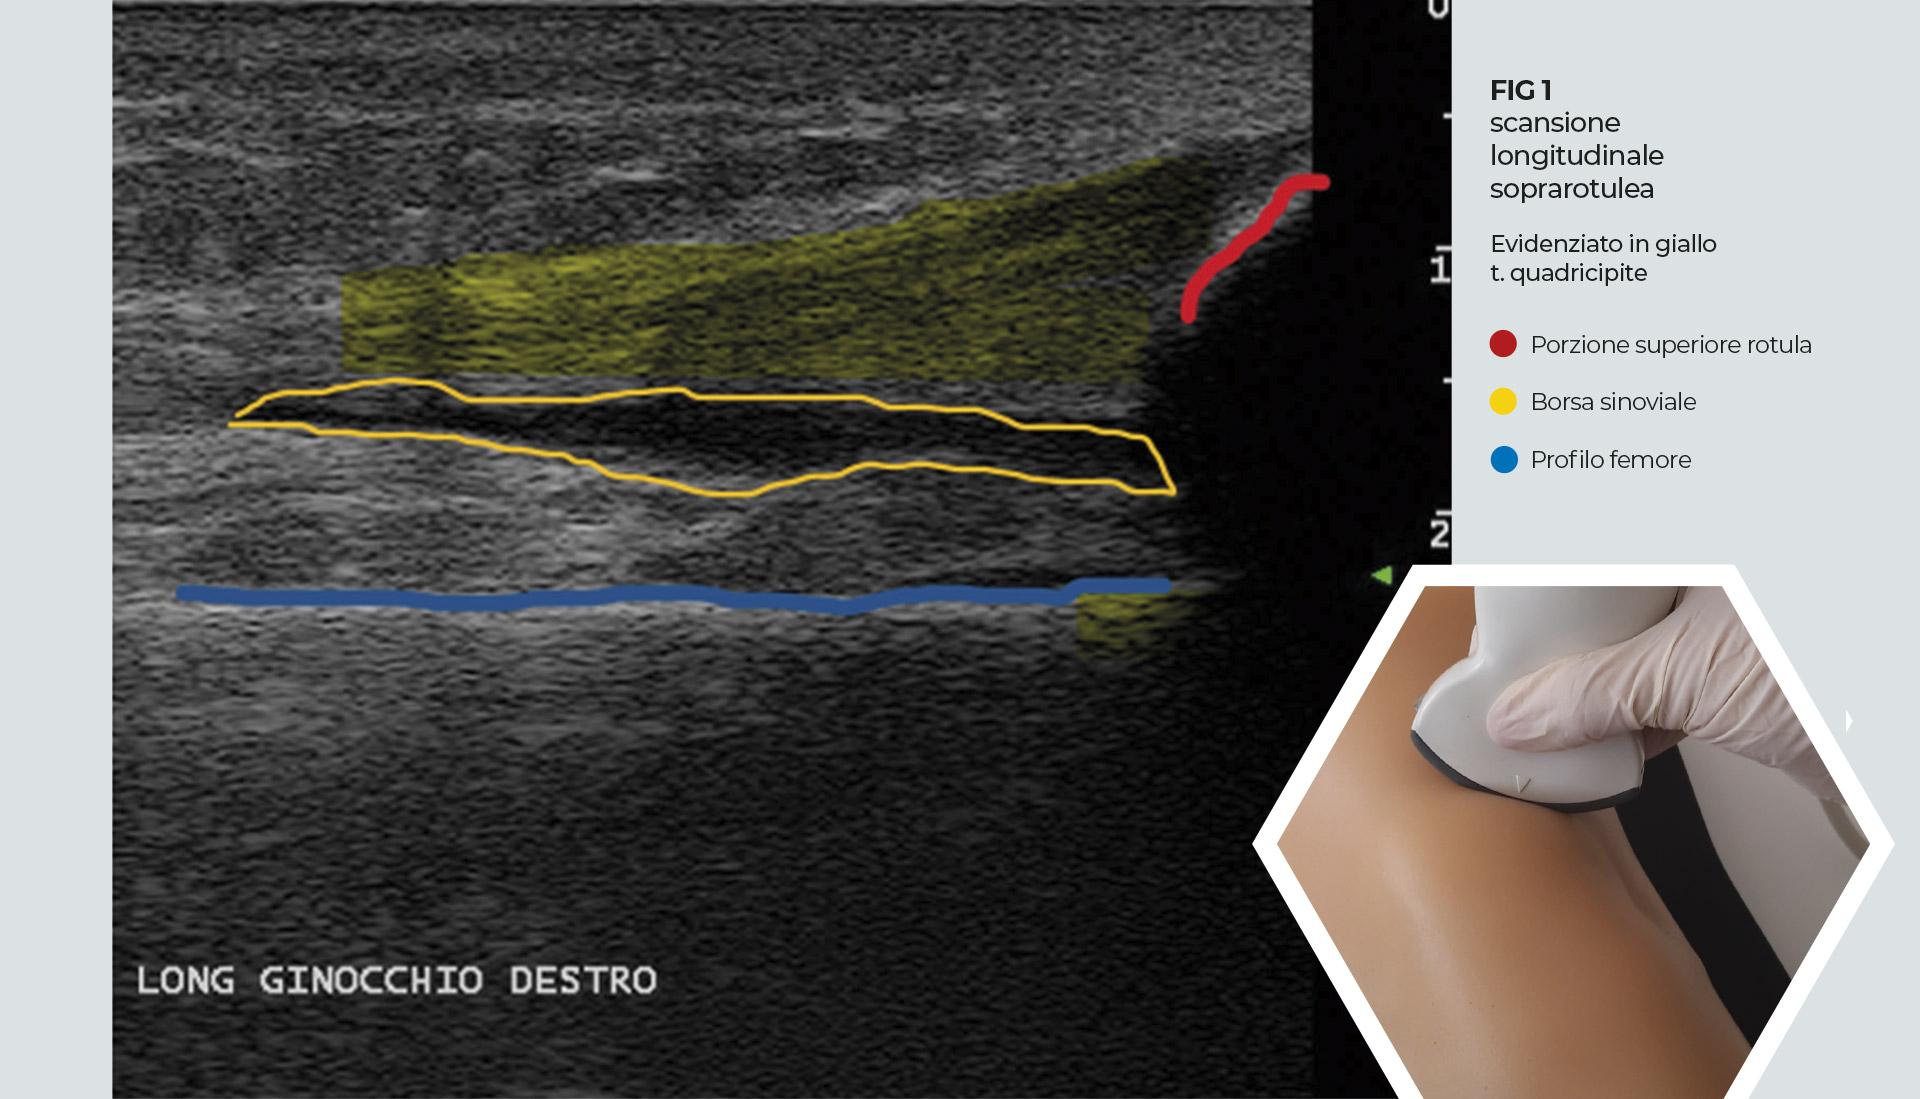

• Paziente in decubito supino, ginocchio flesso a 20-30° (cuscino sottopopliteo). Posizionare la sonda lineare in scansione longitudinale identificando, inferiormente, il polo superiore della rotula e il tendine del quadricipite con il suo aspetto stratificato, per i fasci tendinei provenienti da retto femorale, vasto laterale e vasto mediale. Al di sotto della parte distale del tendine si trova il recesso sinoviale sovrarotuleo, come uno spazio ipo-anecogeno (di dimensioni variabili in base alla quantità di liquido sinoviale).

Identificato il recesso sinoviale si ruota la sonda di 90° con una scansione trasversale del recesso, al di sopra della corticale del femore. Identificato il punto di iniezione laterale, sottorotuleo, parallelo all’asse maggiore della sonda, si pratica l’iniezione con ago 21/22 G, guidati dalla visualizzazione ecografica dello stesso e dal rigonfiamento della borsa conseguente all’introduzione del farmaco iniettato. Importante stabilizzare la sonda con le dita della mano che la manovra a contatto con la pelle, evitare una pressione eccessiva da parte della stessa ed eseguire piccoli movimenti.